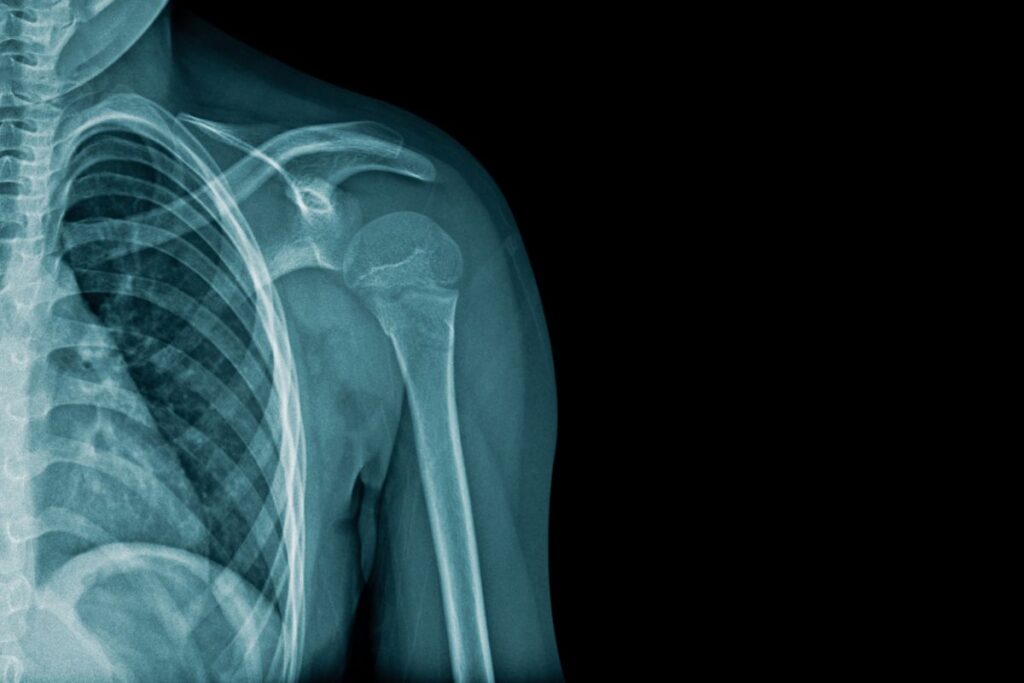

Quando há suspeita de alterações estruturais, solicitamos exames de imagem: o raio-X auxilia na avaliação articular e na exclusão de artrose, o ultrassom permite análise dinâmica de tendões e bursas, e a ressonância magnética é o exame mais completo para identificar lesões do manguito rotador, labrum e processos inflamatórios mais profundos.